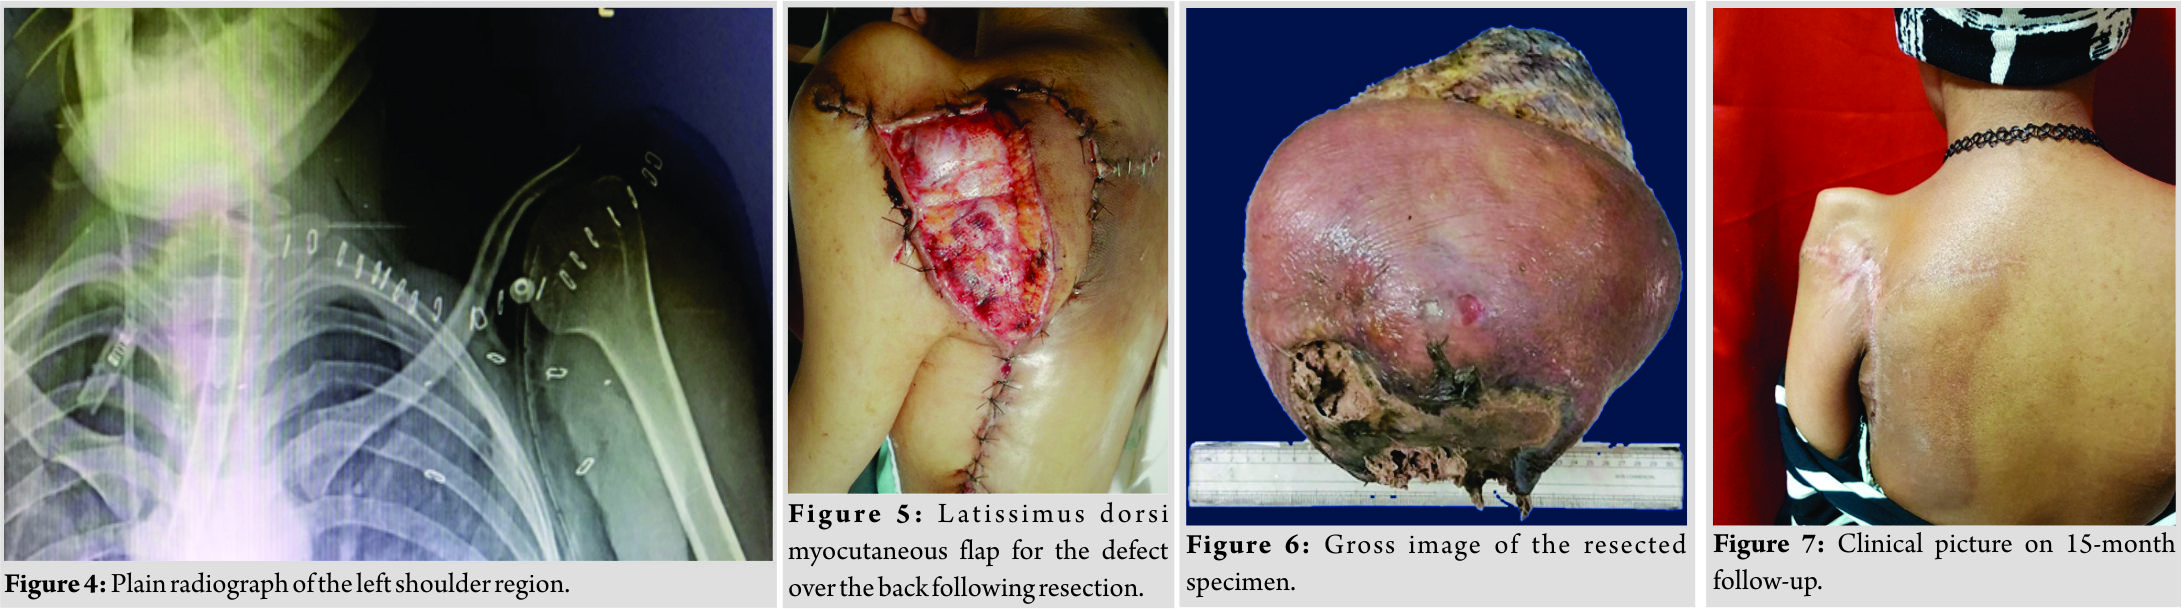

A 24-year-old female presented with a massive fungating mass over the left upper back and shoulder. The patient gave a history of swelling over the left upper back, which was insidious in onset and gradually progressed over the past 2 years. Incisional biopsy over the most prominent aspect of the swelling was performed elsewhere about 1 year ago, a provisional diagnosis of ES of the left scapula was made and the patient was started on chemotherapy and operated following 3months of chemotherapy. The wound following surgery did not heal and an ulcer developed over the operated site which rapidly increased in size. Neoadjuvant chemotherapy was started and the regimen was changed multiple times over the next 9months as the tumor did not respond and swelling continued to progress in size. In view of the size and nature of the lesion, wound, and associated complications, the patient was advised forequarter amputation of the left upper limb at multiple centers in her country, which she refused and was finally referred to our hospital for further management. On presentation, a huge fungating mass was noticed over the left upper back and shoulder region with active bleeding and foul-smelling discharge from the ulcer (Fig. 1). The patient was febrile and unable to use the left upper limb due to the size of the lesion and excruciating pain. Magnetic resonance imaging of the shoulder and upper back showed a T1 isointense and T2 heterogeneous high-signal intensity lesion which measured 18 cm ×27cm × 26cmin size, with multiple fluid levels, degenerative cystic changes, hemorrhage, areas of necrosis, and infiltration of periscapular musculature (Fig. 2). On computed tomography (CT) scan, tumor was ill defined with heterogeneous attenuation, multiple areas of cystic changes, and gross osteolysis of the scapula. However, the shoulder joint, chest wall,and the brachial plexus were not involved, axillary vascular bundle was displaced anteriorly without signs of infiltration. Whole body positron emission tomography-CT scan showed no signs of pulmonary or distant metastasis. Diagnosis of Ewing’s sarcoma was made by histopathological examination of needle biopsy sample from the swelling, which showed sheets of small, round, and uniform cells with scanty cytoplasm, separated by fibrous strands with few mitosis and minimal stroma (Fig. 3). CD99 was positive on immunohisto chemistry. In view of the clinical condition of the patient up front surgery was performed, following antibiotics to control infection, blood transfusions to correct anemia, and selective arterial embolization of feeding vessels. The patient underwent enbloc excision of the tumor mass by total scapulectomy. The ulcer was covered with an adhesive sterile surgical drape; circumferential incision was made around the tumor mass including 3cm of pinchable uninvolved skin. Axillary vascular bundle and the brachial plexus were dissected and isolated from the tumor mass. Arthrotomy of the left shoulder was performed as a layer of the capsule of the joint was also removed. Periscapular musculature was also removed along with the tumor mass. Frozen section from the surrounding soft tissue and chest wall was negative for residual tumor cells. The humeral head was secured to the lateral end of the clavicle (Fig. 4), and the defect over the back following resection was closed by negative pressure dressing and subsequentlycovered2days later with latissimus dorsi free pedicle flap (Fig. 5). The humeral head was plain radiograph of the left shoulder region following resection.Diagnosis of ES was confirmed by histopathological examination of the resected specimen and all the resected surgical margins were free of tumor (Fig. 6). 3 weeks after surgery, concomitant radiotherapy and adjuvant chemotherapy (6 cycles of vincristine, doxorubicin, and cyclophosphamide alternating with ifosfamide and etoposide) were started.The patient also underwent autologous stem cell transplantation following adjuvant chemotherapy. There were no neurological or vascular deficits in the operated limb following the procedure and the patient on follow-up had good functional range of motion of the left shoulder and full range of motion of the left elbow, wrist, and fingers. On final follow-up of 3 years, the patient showed no signs of local recurrence (LR) or metastasis and had returned to her prior vocational status (Fig. 7).

The patient was febrile and unable to use the left upper limb due to the size of the lesion and excruciating pain. Magnetic resonance imaging of the shoulder and upper back showed a T1 isointense and T2 heterogeneous high-signal intensity lesion which measured 18 cm ×27cm × 26cmin size, with multiple fluid levels, degenerative cystic changes, hemorrhage, areas of necrosis, and infiltration of periscapular musculature (Fig. 2). On computed tomography (CT) scan, tumor was ill defined with heterogeneous attenuation, multiple areas of cystic changes, and gross osteolysis of the scapula. However, the shoulder joint, chest wall,and the brachial plexus were not involved, axillary vascular bundle was displaced anteriorly without signs of infiltration. Whole body positron emission tomography-CT scan showed no signs of pulmonary or distant metastasis. Diagnosis of Ewing’s sarcoma was made by histopathological examination of needle biopsy sample from the swelling, which showed sheets of small, round, and uniform cells with scanty cytoplasm, separated by fibrous strands with few mitosis and minimal stroma (Fig. 3). CD99 was positive on immunohisto chemistry. In view of the clinical condition of the patient up front surgery was performed, following antibiotics to control infection, blood transfusions to correct anemia, and selective arterial embolization of feeding vessels. The patient underwent enbloc excision of the tumor mass by total scapulectomy. The ulcer was covered with an adhesive sterile surgical drape; circumferential incision was made around the tumor mass including 3cm of pinchable uninvolved skin. Axillary vascular bundle and the brachial plexus were dissected and isolated from the tumor mass. Arthrotomy of the left shoulder was performed as a layer of the capsule of the joint was also removed. Periscapular musculature was also removed along with the tumor mass. Frozen section from the surrounding soft tissue and chest wall was negative for residual tumor cells. The humeral head was secured to the lateral end of the clavicle (Fig. 4), and the defect over the back following resection was closed by negative pressure dressing and subsequentlycovered2days later with latissimus dorsi free pedicle flap (Fig. 5). The humeral head was plain radiograph of the left shoulder region following resection.Diagnosis of ES was confirmed by histopathological examination of the resected specimen and all the resected surgical margins were free of tumor (Fig. 6). 3 weeks after surgery, concomitant radiotherapy and adjuvant chemotherapy (6 cycles of vincristine, doxorubicin, and cyclophosphamide alternating with ifosfamide and etoposide) were started.The patient also underwent autologous stem cell transplantation following adjuvant chemotherapy. There were no neurological or vascular deficits in the operated limb following the procedure and the patient on follow-up had good functional range of motion of the left shoulder and full range of motion of the left elbow, wrist, and fingers. On final follow-up of 3 years, the patient showed no signs of local recurrence (LR) or metastasis and had returned to her prior vocational status (Fig. 7).